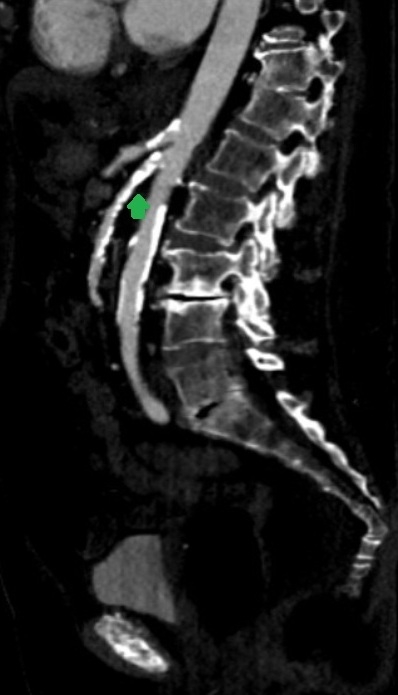

CTA revealed bulky calcifications with severe short-segment stenosis in the proximal superior mesenteric artery (SMA), minor proximal narrowing in the celiac artery, and some calcifications at the origin of the inferior mesenteric artery (Image 1).